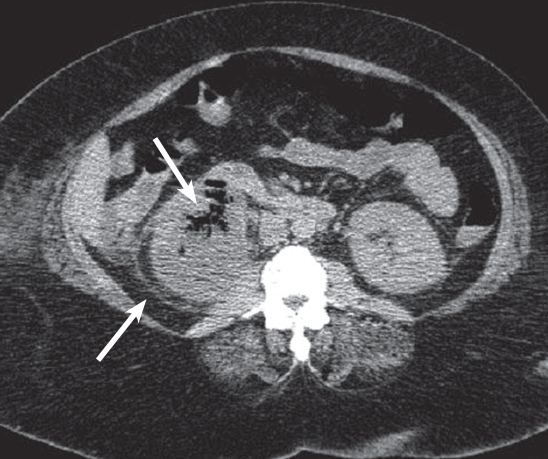

Laboratory testing. White blood cell count was 17,300/µL with 86% neutrophils and 9% bands, platelet count was 157,000/µL, blood urea nitrogen level was 64 mg/dL, and creatinine level was 5 mg/dL. Urinalysis showed 3+ proteinuria, glycosuria, positive leukocyte esterase, as well as pyuria and bacteria. A CT scan of the abdomen (Figure) revealed an enlarged, nonhydronephrotic right kidney with perinephric stranding, gas within the cortex (thick arrow) and perinephric spaces (thin arrow), as well as inflammation and stranding around the right proximal ureter.